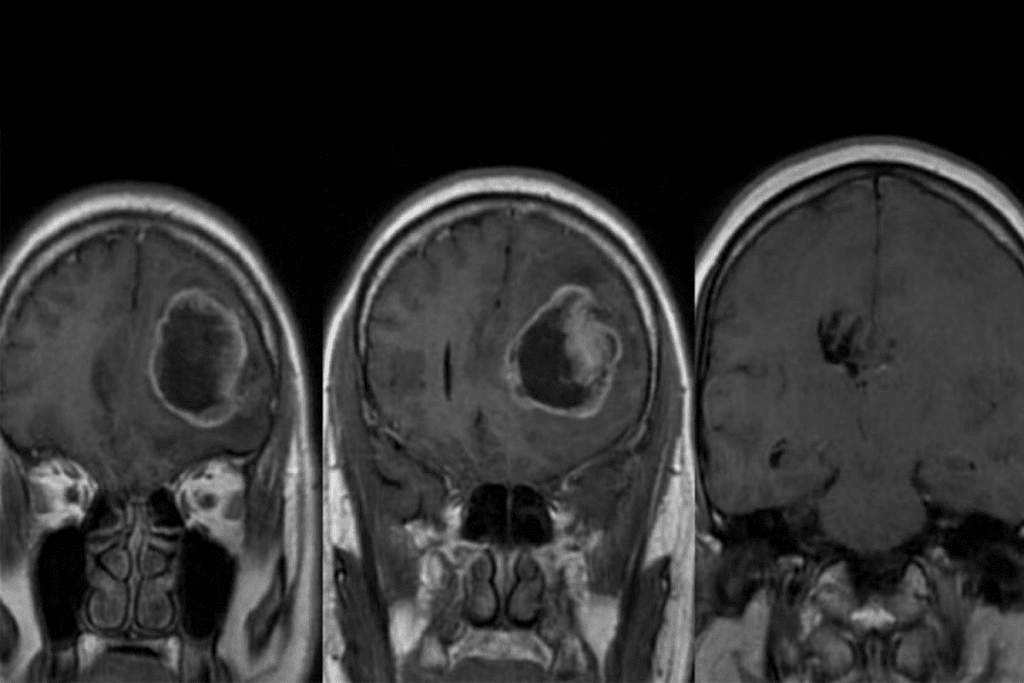

Neuroimaging Techniques (MRI, CT, PET)

Neuroimaging is a big deal in finding brain tumors. MRI, CT scans, and PET scans are at the top of the list for seeing tumors clearly.

- MRI: Gives detailed pictures of soft tissues like the brain, without harmful radiation.

| MRI | High-resolution soft tissue imaging, no radiation | Detailed tumor anatomy, treatment planning |

After abnormal CBC results, more tests are done. These include MRI or CT scans and cerebrospinal fluid analysis. Sometimes, a tissue biopsy is needed for a clear diagnosis.